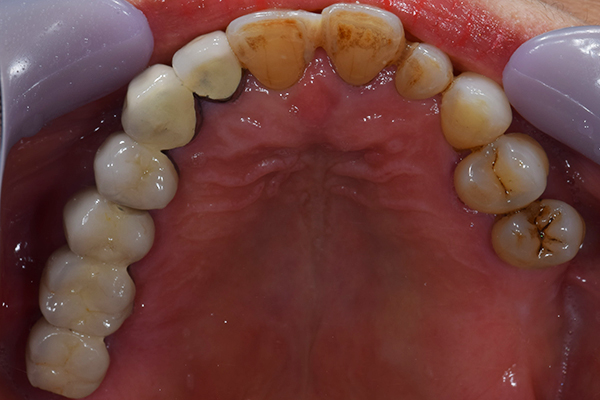

ケース1(自費の部分入れ歯)

前歯が折れて当院にいらっしゃいました。 過去に下の入れ歯を作ったが、合わなくなってずっと入れ歯をいれていらっしゃらない患者様でした。 これは奥歯で噛むことができないため、前歯で噛むことを繰り返したために、負担に耐えられなくなった前歯が折れてかぶせ物ごと 外れてしまったのだと考えられます。 痛くない、違和感の少ない、下の入れ歯を作ることがこの方のゴールであると考えられました。

シリコンで精密な型取りを行いました。

噛み合わせチェックです。 奥歯でしっかりものが噛める様に高さを決めていきました。

金属を使用して、薄く違和感が少ない入れ歯が完成しました。 また、見た目にも気を使い、バネが見えにくい様な構造にしました。

入れ歯をお口の中にいれた状態です。前歯もMTMといって、歯を少し引っ張り出す処置を行なったことで、しっかり残せて、またかぶせ物をしました。

年齢 70歳・女性

主訴 前歯が取れた

治療期間 8ヶ月

治療費 .MTM:110,000円

.ファイバーコア:16,500円

.E-maxクラウン:110,000円

.義歯:660,000円

治療方針 長年使ってきた義歯の人工歯が磨耗し、臼歯部での咬合がすくなくなり、前歯部での接触が強くなったことで生じた前歯の破折なので、義歯も作り変える必要がある。

治療内容 前歯部MTMと同時に審美面の回復。

MTM中に義歯の作成も同時に行う。

最終的に義歯と前歯のクラウンを同時にいれる。

義歯は下顎で、しっかり噛めること、違和感の少ないものという希望があったため、なるべく入れ歯を薄く作成するために金属をしようした義歯とした。

また、見た目もあまり義歯が目立たない様に、バネの部分を見えにくいように作成した。

特記事項 歯にもともと入っていた金属の種類によっては、歯自体の変色を治療で変えられないこともある。 義歯は作ってから痛みがでることがありますが、それは調整を行うことで痛くなくすることができます。